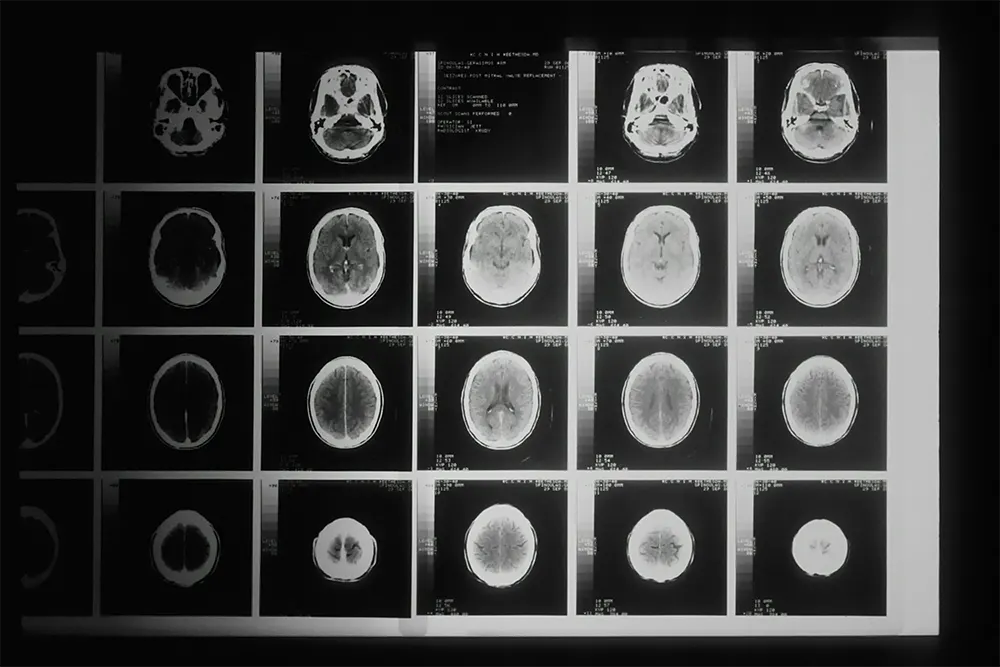

Um novo estudo realizado pela Universidade da Califórnia em São Francisco (UCSF), publicado nesta semana na revista científica JAMA Internal Medicine, trouxe à tona preocupações sérias sobre os riscos associados ao uso excessivo de tomografias computadorizadas (TCs) nos Estados Unidos. Segundo os pesquisadores, a exposição à radiação ionizante durante esses exames pode ser responsável por até 5% dos diagnósticos de câncer anuais no país.

Em 2023, cerca de 93 milhões de exames de TC foram realizados nos EUA, o que, segundo os autores, poderia resultar em até 103 mil novos casos de câncer — número três a quatro vezes maior do que o estimado anteriormente.

O estudo se destaca por usar dados individualizados e mais precisos sobre doses de radiação e frequência de exames, oferecendo um panorama mais realista sobre os riscos. A análise foi feita com base em 93 milhões de exames realizados em 61,5 milhões de pacientes.